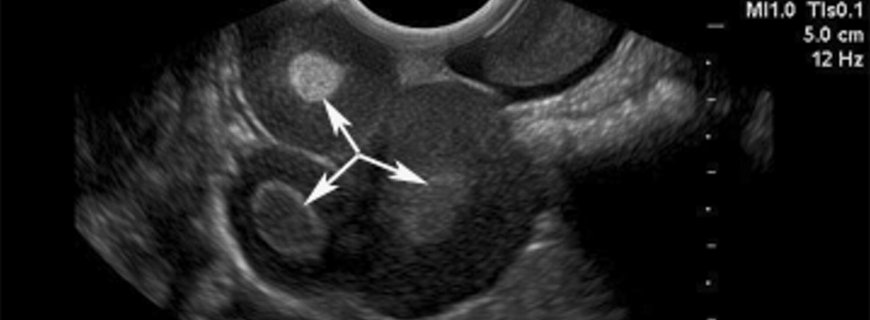

Yumurtalık kistleri yumurtalığın içinde ya da yüzeyindeki sıvı ile dolu keselerdir. Çoğu yumurtalık kisti fizyolojiktir ve genellikle belirtisiz seyreder. En sık görülen fizyolojik kistler folliküler...

Endometriomalar, rahim iç duvarına benzer tipte bezlerin bulunabildiği iyi huylu, bir yumurtalık kistidir. Bu hastalarda genellikle karın içinin diğer bölgelerinde de endometriozis denen benzer hastal...

Seröz Kistadenoma Nedir?Seröz kistadenoma tüm yaşlarda yumurtalıkların en sık iyi huylu tümörüdür. Fizyolojik kistlerdekinin aksine, bu tümörler kötü huylu dönüşüm potansiyeline sahiptirler. %15 kad...